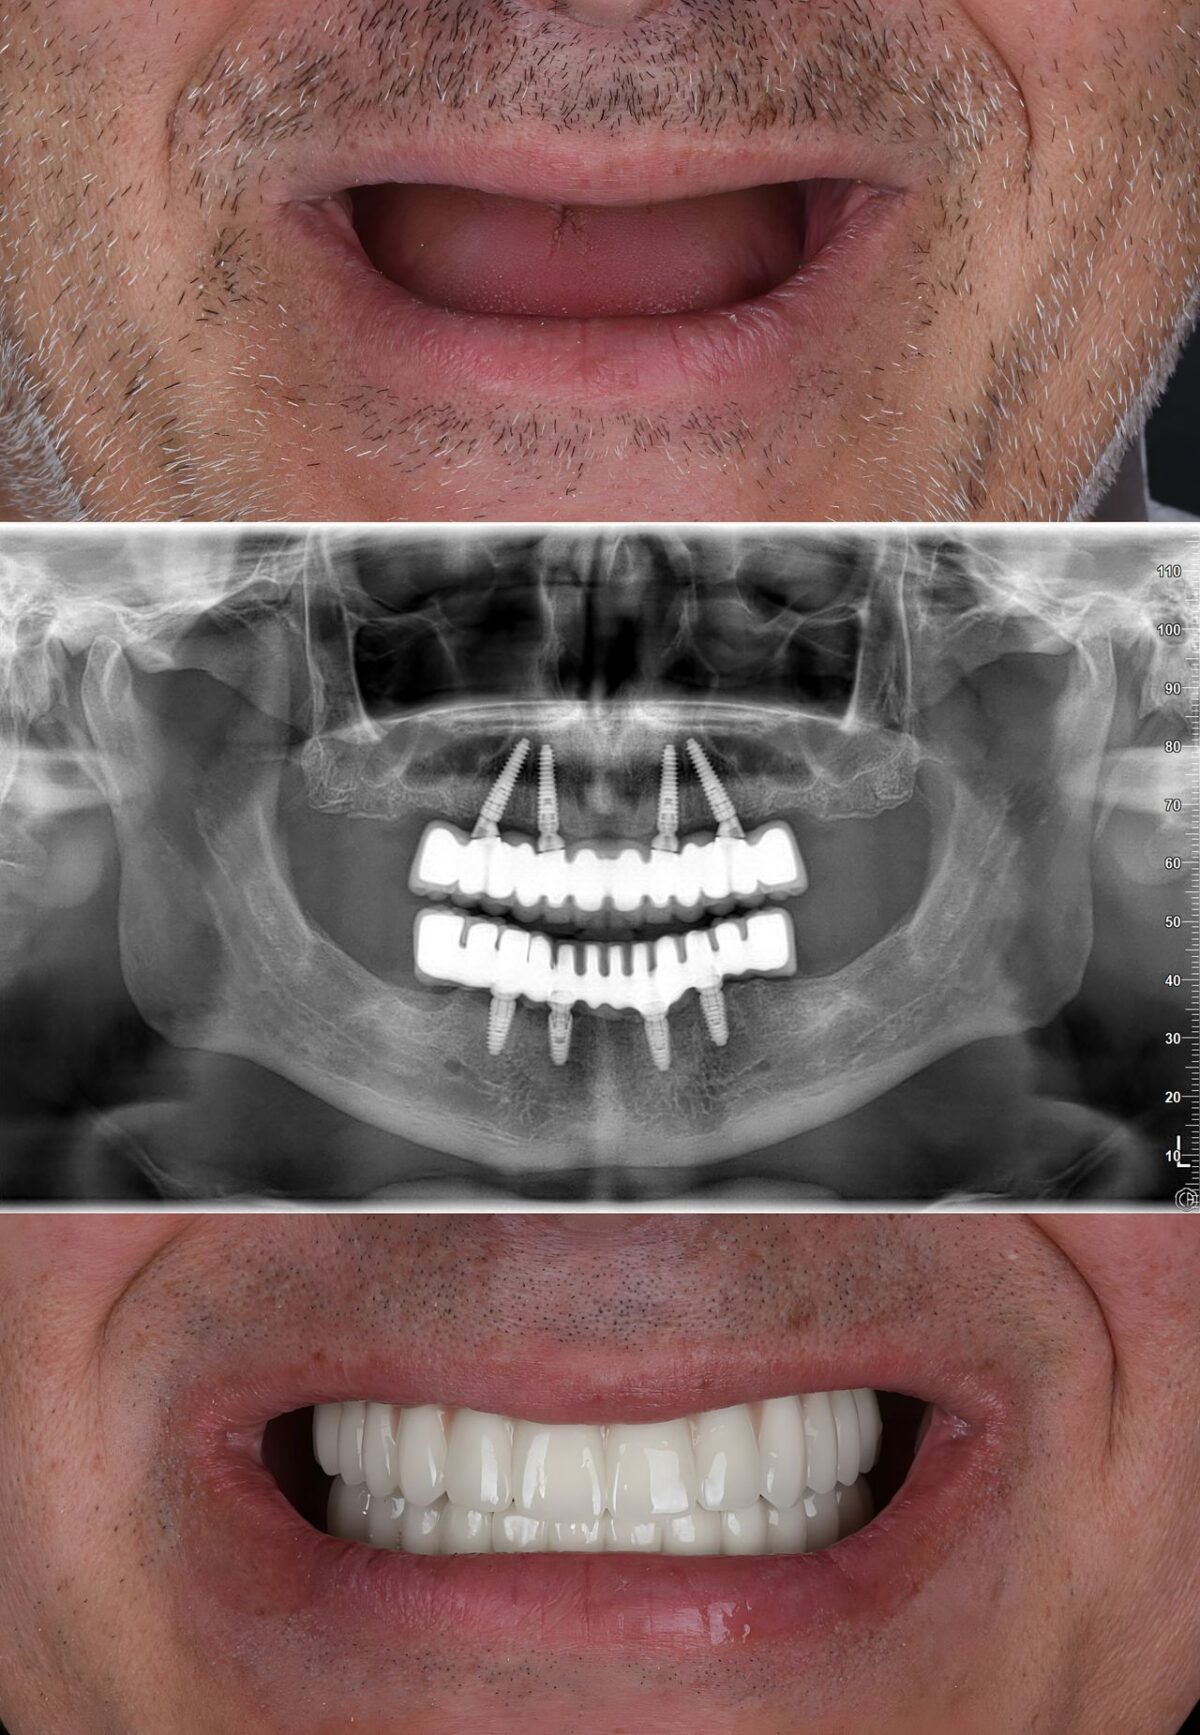

A dental implant is a small titanium post that replaces the root of a missing tooth. Once gently placed into the jawbone, it naturally fuses with the bone to form a stable foundation for a crown, bridge, or denture.

Unlike removable dentures, implants are a permanent tooth replacement that look, feel, and function just like natural teeth — allowing you to enjoy your favourite foods and smile confidently every day.

A secure and stable alternative to removable dentures — no slipping, adhesives, or discomfort.